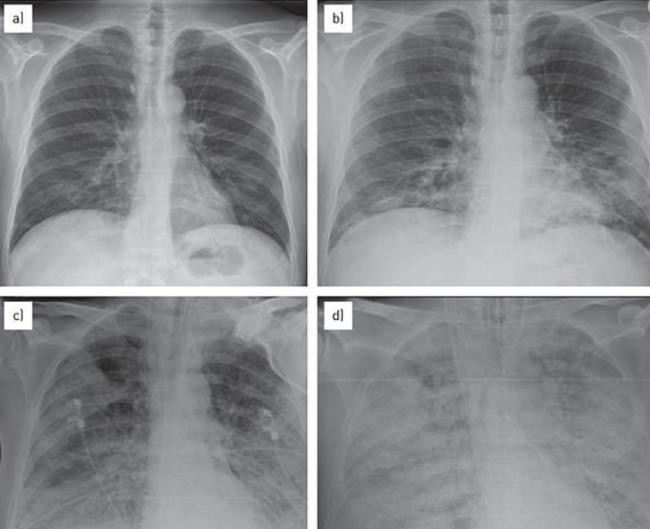

注意预防 秋冬季节本就是北美流感高发季节,但2023年冬天似乎有些不寻常,一种“白肺”疫情正在悄然蔓延,已经在美国爆发,引发一波儿童肺炎感染浪潮! 据外媒报道,美国有两个州现在儿童感染肺炎的病例正在激增,已经让医生们开始担心,这股疫情会扩散开来。 距离俄亥俄州辛辛那提郊外仅30英里的沃伦县,现在已经有142宗确诊“白肺综合症”的儿童病例,且一直在攀升,当地卫生官员表示这个数字已经“极高”。 多个学区都接连出现确诊病例,响起警报。 本周三,卫生官表示:“这不仅高于本地的平均水平,且符合俄亥俄州卫生部对疫情的定义。” 与此同时,马萨诸塞州西部还出现了大量“行走性肺炎”病例。 这个“行走性肺炎”是由细菌和病毒感染的混合物引起的,是一种比较温和的肺部疾病,患者会出现发烧和咳嗽的症状,但是没有痰。 ![]() ![]() 儿科医院的凯利医生接受采访时表示,现在正是呼吸道病毒 RSV 的流行季节,很多孩子患有上病毒性呼吸道感染、咳嗽、流鼻涕,还有一些发烧,对肺部也有影响。 ![]() 现阶段,80%患有“行走性肺炎”的儿童是由于首次感染RSV引起的,20%病例是由细菌引起的,可用抗生素治疗。 对于此波疫情,美国卫生当局也提出了几种可能性,其中之一就是大流行期间的封锁、戴口罩和关校一定程度上削弱了儿童的免疫力,使他们在疫后更容易患上季节性疾病。 康涅狄格州耶鲁大学医学院传染病专家斯科特·罗伯茨(Scott Roberts)博士表示,“这可能是已知病原体的复发,但由于孩子们对它们的免疫力低下,这些病原体的影响更大。” 这两个州目前的疫情都不是由新型病原体引起的,也不是所有的肺炎病例都是由同一感染引起的,而是几种季节性细菌和病毒的混合物同时袭击。 人们开始担心,这波肺炎蔓延,会让美国今年冬天可能爆发不堪重负的感染疫情。对此,CDC表示现在全国范围内尚未出现什么“不寻常”的数据。 除了这两个州,数据显示其他州的儿童肺炎水平遵循“季节性趋势”,没有任何异常情况,但CDC正在继续监测。 俄亥俄州卫生部门正在调查究竟是什么引发了疾病浪潮,疫情爆发的地区人口有200万左右,目前大部分患者都是儿童,平均年龄在8岁左右,有的孩子只有3岁。 ![]() 经检测,许多确诊儿童的肺炎支原体、链球菌和腺病毒检测都呈阳性。大多患者都有发烧、咳嗽、疲劳的症状,目前尚不清楚有没有出现死亡病例。 医生表示,大多数感染都是轻微的,但最近刚感染过呼吸道疾病的人面临更高的风险。 “(现阶段)我们不认为这是一种新型的呼吸道疾病,而是通常人们看到的肺炎,但病例数量正在大幅增加”。 随着假期的临近,大家都会回家团聚,与亲朋好友聚餐,卫生官也提醒所有人,需要采取必要的预防措施。“勤洗手,咳嗽时捂住口鼻,生病时待在家里,并及时接种疫苗。” 通常而言,细菌性呼吸道感染通常每隔几年就会爆发一次,肺炎支原体感染往往每三到七年就会达到顶峰。 只不过,2020年新冠疫情爆发以来,这种疾病还没有达到感染顶峰。 马萨诸塞州的医生表示,这次疫情的主要问题是呼吸道合胞病毒RSV,这是一种呼吸道病毒,每年导致10000多名美国人死亡,其中大多数是幼儿和老人。 “现在就是RSV的高发季节,我们看到了很多孩子患有上层病毒性呼吸道感染、咳嗽、流鼻涕、发烧,而RSV会导致下层病毒性呼吸道感染,传播到肺部。 ![]() 欧洲的荷兰和丹麦也正在经历类似的感染潮,“神秘”肺炎病例达到峰值。 秋冬本来就是各种呼吸道疾病的流行季节,年底了,各种聚会越来越多,希望大家都做好预防措施。 |